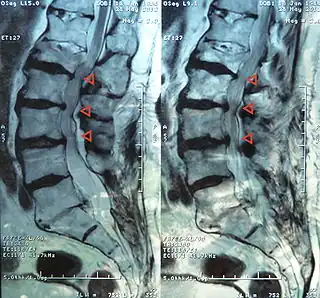

Estenosis de canal a nivel L4-3-2-1 | ||

El término estenosis medular lumbar incluye la estenosis del canal espinal, el receso lateral y los agujeros o forámenes intervertebrales siendo más común en los niveles L2 a L5 y constituye una de las causas más comunes de dolor en la espalda y en las extremidades inferiores por opresión de la médula y de las raíces nerviosas espinales.[2]

Además de los síntomas referidos y de los signos clínicos al examen físico, el médico puede ordenar una o más pruebas, tales como: Radiografías, imagen de resonancia magnética (IRM), tomografía axial computarizada (TAC), mielograma y gammagrafía ósea .